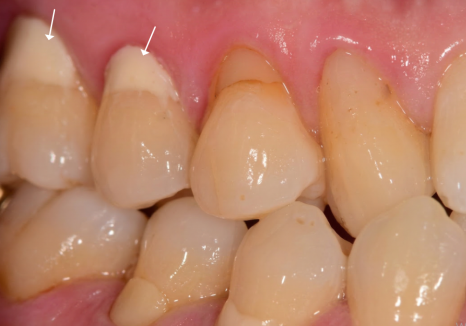

이 환자분은 치아 뿌리 쪽이

아주 깊게 패어 있는 모습인데요.

오랜 세월 동안 마모가 서서히 진행되어,

육안으로 봐도 치아 안쪽의 신경이

드러날 정도로 심각한 상태였습니다.

보통 이 정도로 패여서 신경이 노출되면

물만 닿아도 자지러지게 아픈 게 정상이에요.

그래서 대부분은 신경치료를 하고

치아를 씌워주는 크라운 치료를 진행하게 됩니다.

하지만 이 환자분은

통증이나 시린 증상을 거의 못 느끼고 계셨어요.

바로 '신경의 석회화' 때문인데요.

아주 오랜 시간에 걸쳐 천천히 마모가 진행되면

우리 몸은 스스로를 보호하기 위해

신경관 안쪽을 딱딱하게 굳히거나

뒤로 후퇴시킵니다.

신경이 무뎌진 상태가 된 것이죠.